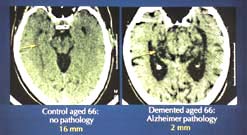

|  |  | | Changes in the brain due to AD | Alzheimer’s Disease

In the first of a new series of Frontiers, Peter Evans talks to doctors and researchers about our current state of knowledge of Alzheimer’s Disease. We know that tangles of fibrous tau protein build up inside the nerve cells, and that amyloid plaques form in the synapses between cells. But while therapies that slow the rate of memory loss are now available, we’re still a long way from discovering the mechanism that triggers the onset of Alzheimer’s Disease.